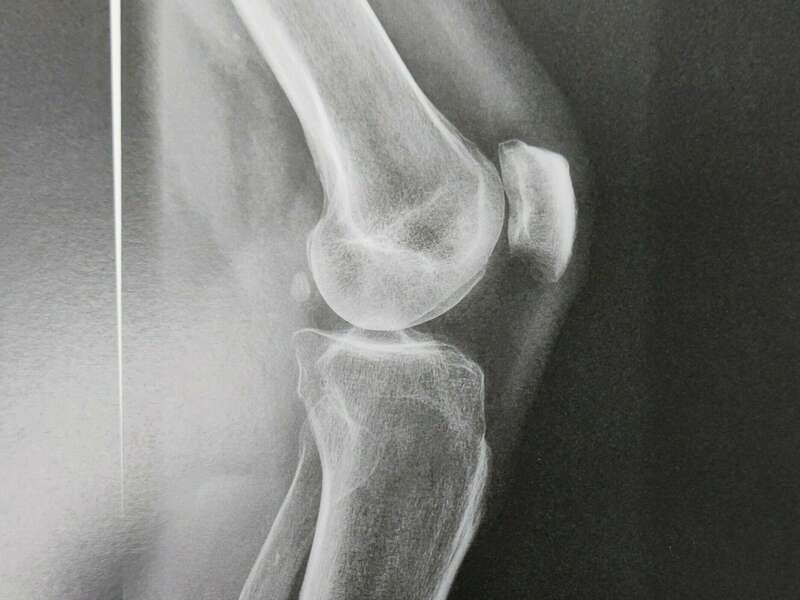

L’articulation du genou assure la jonction entre le fémur (condyles fémoraux), le plateau tibial et la rotule (patella). Elle se compose de deux articulations : l’articulation fémoro-patellaire entre le fémur et la rotule et l’articulation fémoro-tibiale qui elle-même se divise en deux compartiments (interne et externe).

L’ensemble des zones de frottement entre les différents os est recouvert d’un cartilage d’une épaisseur d’environ 3 à 4 mm d’épaisseur qui facilite le glissement entre les différentes surfaces articulaires.

L’arthrose désigne un processus d’usure du cartilage liée au vieillissement. Ce n’est pas une fatalité liée à l’âge. Elle cause des dommages irréversibles du cartilage qui perd au fur et à mesure son rôle de surface de glissement et d’amortisseur. La pression sur l’os s’accroît à mesure que l’épaisseur cartilagineuse diminue.

Des excroissances osseuses, appelées ostéophytes, des kystes osseux et des ulcérations cartilagineuses se forment progressivement. En réponse, la membrane synoviale devient inflammatoire et produit un liquide synovial. L’excès de pression articulaire et l’inflammation sont les causent des douleurs de genou. La perte de congruence de l’articulation entraîne quant à elle, une diminution de la mobilité articulaire.

Elle sera confirmée par des examens radiologiques tels que des radiographies du genou. En cas de doute diagnostic ou afin de rechercher d’éventuelles lésions associées, un scanner et/ou une IRM pourront être prescrits.